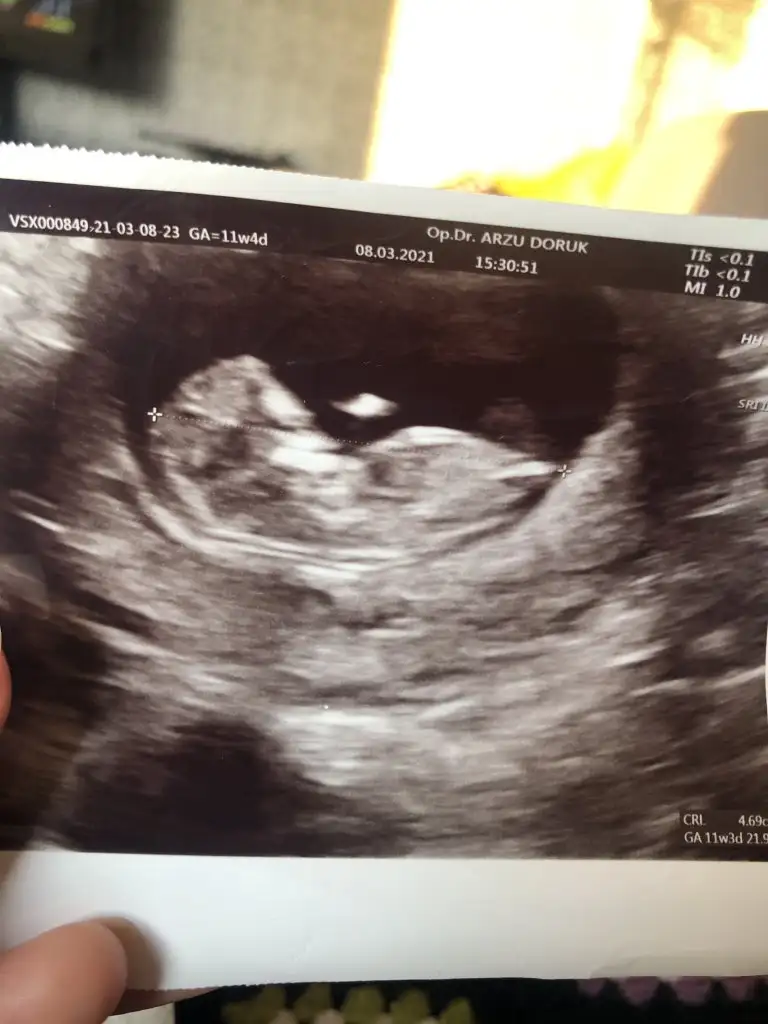

Merhabalar biz de bugün kontrole gittik. Henüz cinsiyeti öğrenemedik ense kalınlığı 0.7 dedi dr. Burun kemiğini de gördük. İkili test için kan verdim. Ben toksoplazma testi ikidir hatalı çıkıyor 3. Yü verdim bugün bakalım umarım bu sefer doğru sonuç verir. Eki Görüntüle 2797777

Sizce benimkinin cinsiyet nedir

Merhaba😊 dün kendimi çok yordum akşam birden su geldi oldukça fazla. Bugün de devam edince doktora gideyim dedim ilk haftalarda çok kanamam olduğu için hala devam ediyorum progestana. İnternette araştırınca amniyon sıvısı gelmiş olabilir diye düşündüm 😕 neyseki bu haftalarda olmazmış enfeksiyon belirtisiymiş. Bebişin suyu iyi 😊 ama cinsiyet tahmini yapmadı sizce belli mi